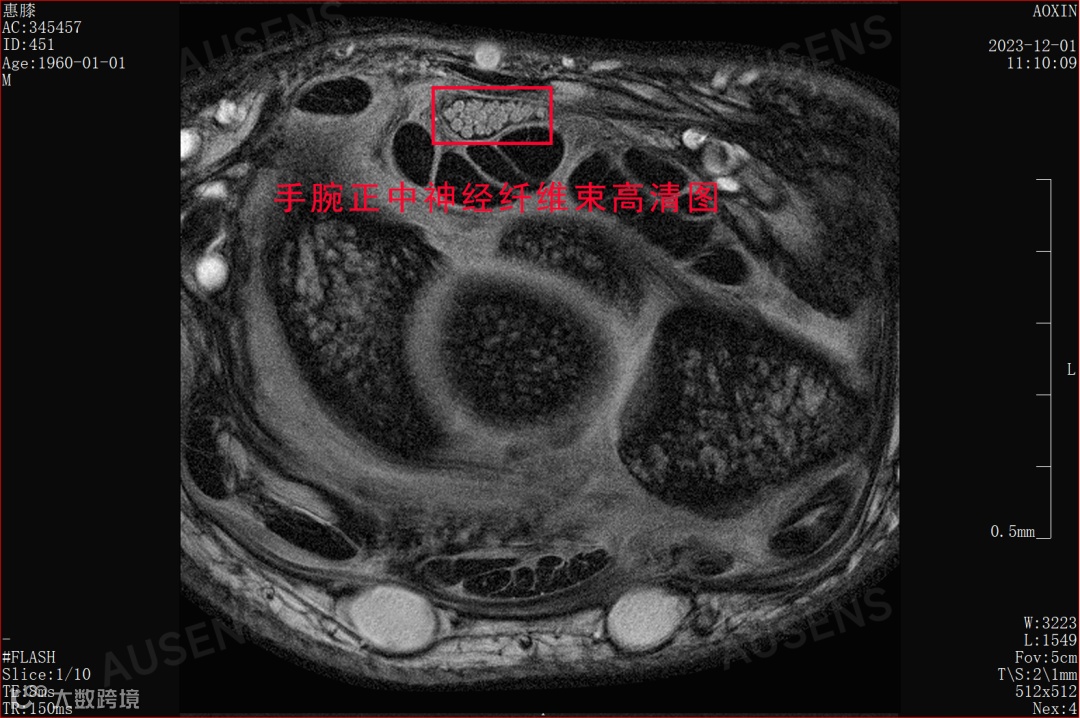

显微级分辨率(可达 90 微米),清晰显示四肢关节的骨骼、软骨、韧带、神经、血管等组织,在早期诊断骨关节炎、软骨损伤等常见疾病中发挥重要作用。

▶ 案例:透过微米级别的腕关节成像,腕管细节和神经纤维束清晰可见,有助于医生发现早期细微病变,为及时干预提供依据。